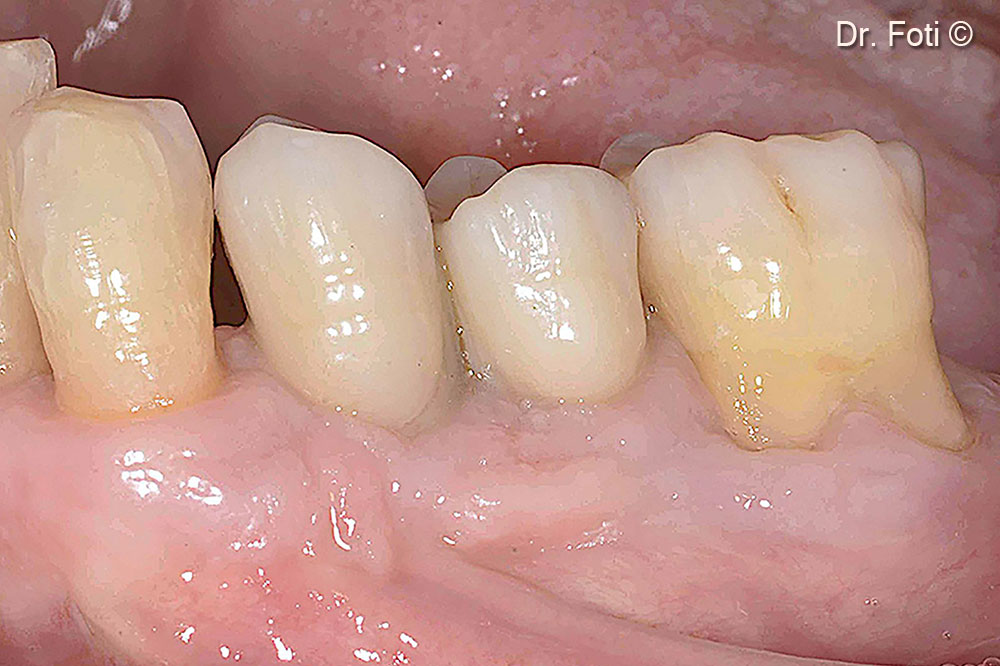

The seven-year follow-up shows creeping of the keratinized mucosa and new papillae formation. The bone peak is stable between the canine and the implant in position 34